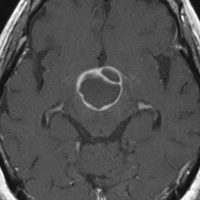

ちょっと大きな頭蓋咽頭腫です

嚢胞(液体が入っている袋)の部分と,腫瘍細胞が固まっている実質部分が入り交じっています。このくらいの大きさになってしまうと,下垂体機能を残すことはとても難しくなります。視神経が圧迫されて視力低下と視野障害を生じます。第3脳室が腫瘍で閉塞していて水頭症になっていますから知能の活動が低下します。

腫瘍を摘出するのに危ないのは,脳の血管の損傷です。左では白く,右では黒く線状に移っているのが太い脳動脈です。これら以外にもたくさんの細い重要な動脈が絡んでいます。

幸いこの患者さんの腫瘍は摘出できて患者さんは元気になりました。でもこのくらいのサイズになると手術がいつもうまくいくとは限りませんし重大な障害が残ることもあります。